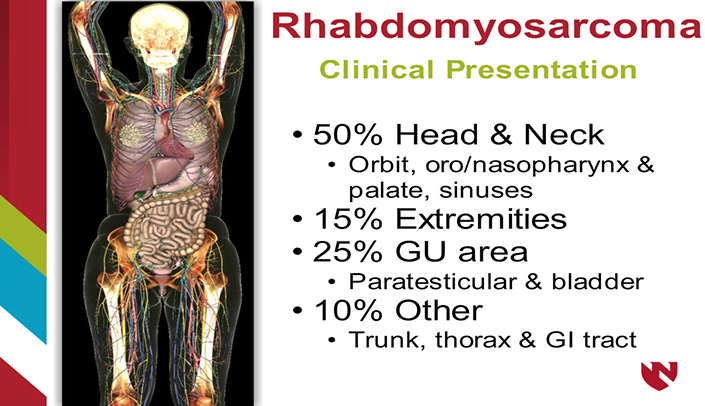

PPT - Rhabdomyosarcoma (RMS): Information On Symptoms, Diagnosis And

www.slideserve.com

www.slideserve.com

rhabdomyosarcoma symptoms treatment rms diagnosis information ppt powerpoint presentation

Rhabdomyosarcoma: A Musculoskeletal Pathology Case Study | E-Gallery

www.unmc.edu

www.unmc.edu

rhabdomyosarcoma musculoskeletal